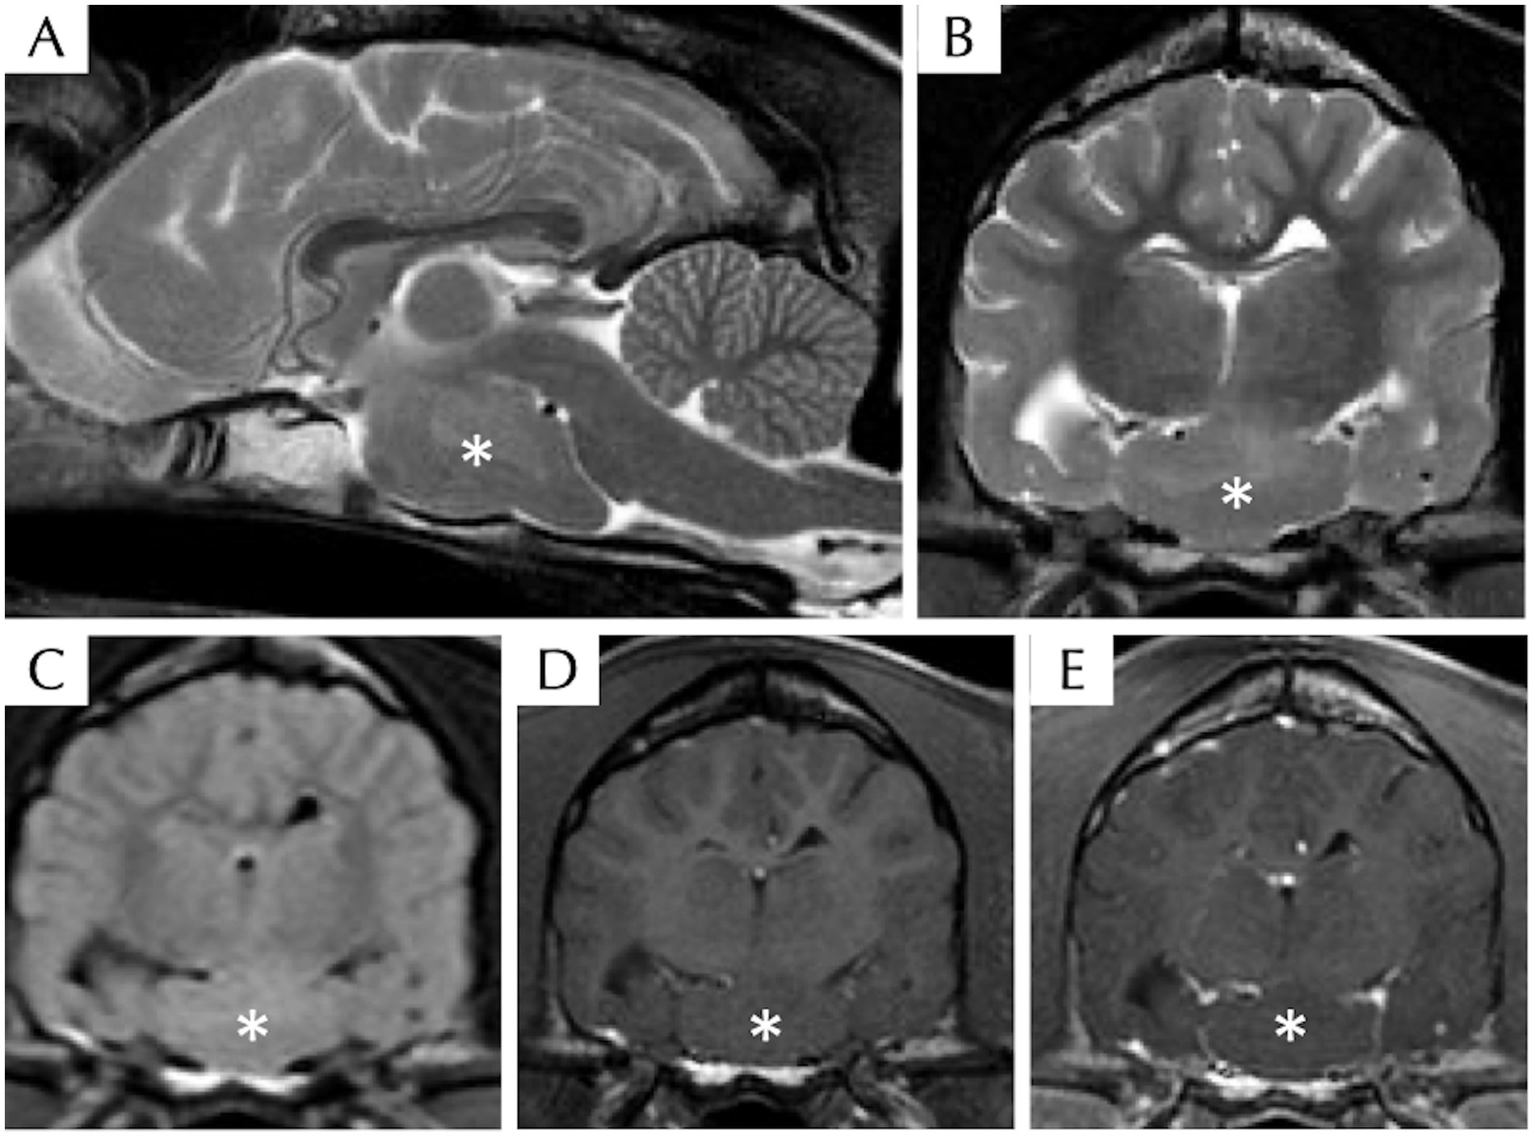

The venous blood gas analysis, haematology, serum biochemistry, bile acid stimulation test, and C-reactive protein were within normal limits. Radiography of the thorax and abdomen were unremarkable. Magnetic resonance imaging of the head revealed a well-defined ovoid suprasellar mass (suspected intra-axial) without contrast enhancement at the level of the middle cranial fossa extending along the cranial base. The lesion was iso-intense to grey matter on T1W, T2W, and FLAIR images (Figure 1). The lesion appeared to be in broad contact with the left ventral margin of the thalamus (hypothalamus). Mass effect, displacement of the pituitary gland cranially with mild compression to the thalamus and midbrain dorsally, and midline shift to the right were present. There were a few regions of mildly heterogeneously T2W and FLAIR hyperintensity compared to the white matter surrounding the lesion, which is likely due to secondary oedema resulting from the compression. Cerebrospinal fluid tap was not attempted, and electroencephalography was declined by the owners. The presumptive diagnosis of HH was based on clinical presentation and characteristic MRI features, whereas neoplasia or inflammatory disease were considered unlikely. Due to the suspected HH diagnosis, approximately 2 mL of EDTA whole blood was also collected by venipuncture for DNA extraction to send for whole genome sequencing with informed consent from the owner, to investigate for possible germline mutations associated with this developmental disorder.

Figure 1

Magnetic resonance imaging of the head of a dog with suspected hypothalamic hamartoma, including T2W sagittal (A), T2W transverse (B), T2 FLAIR transverse (C), T1W pre- (D), and post- (E) contrast transverse sequences. There is a well-defined ovoid T2W, T1W, and FLAIR isointense compared to grey matter intra-axial mass (asterisk) without contrast enhancement at the level of the ventral middle cranial fossa extending along the cranial base within the region of hypothalamus.